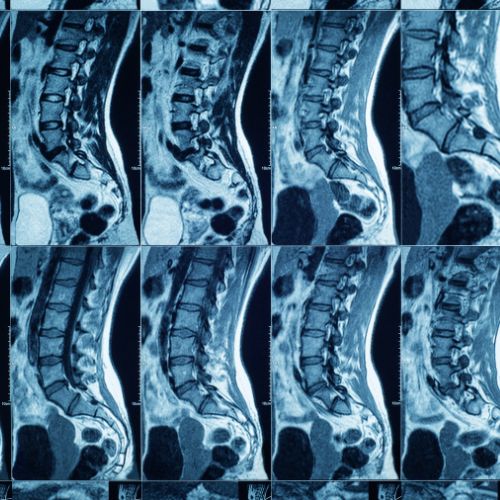

At Stavya: Center for Neck & Back Care, every successful treatment begins with an accurate diagnosis. Our state-of-the-art radiology and diagnostic wing is designed exclusively for spine and nerve-related conditions — offering clarity, comfort, and confidence in every scan.

Advanced Spine Diagnostics

at Stavya Spine Hospital

Wide Tunnel MRI Machine

Our 1.5 T MRI machine provides a convenient and comfortable scanning experience for obese and claustrophobic patients.